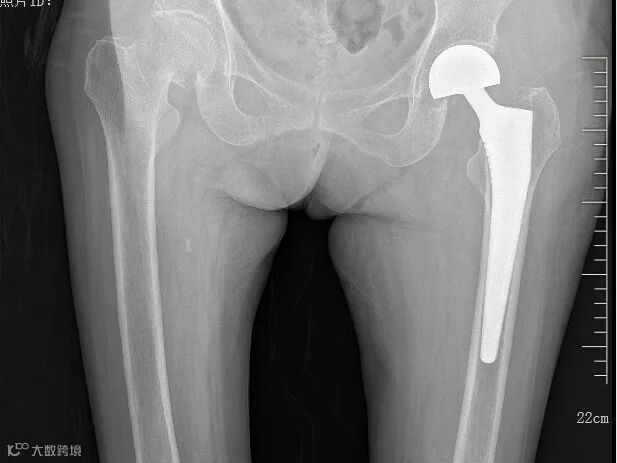

第一次术后影像资料